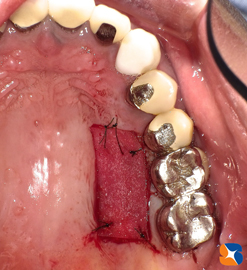

インプラント周囲歯肉を強化する手術:

上あごの分厚い歯肉を下あごへ移植します。

上あごの分厚い歯肉を下あごへ移植しました。

歯肉の手術から1ヶ月後。見事に盤石の歯肉が完成。これなら、如何なる歯ブラシ圧、力に耐えることが出来ます。つまり、一生涯インプラント生活を保証できるのではないでしょうか。